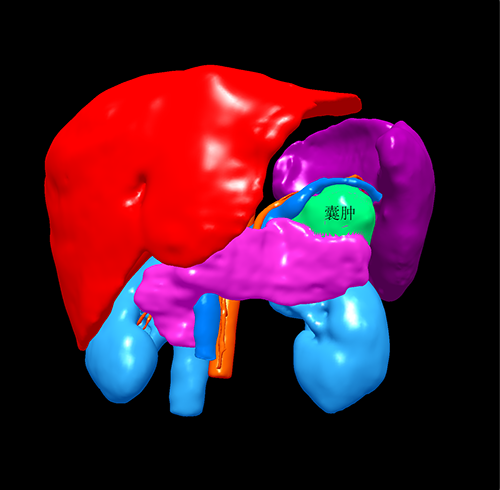

胰尾囊腺瘤---腹腔镜胰尾切除